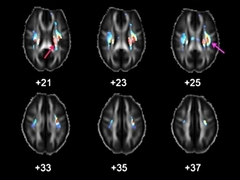

Генетики обнаружили гены, от последовательности которых зависит скорость проведения электрических импульсов в мозге и интеллект их обладателей. Для этого ученые сопоставляли результаты тестов IQ у добровольцев с их генетическими особенностями и результатами магнитно-резонанского сканирования мозга....